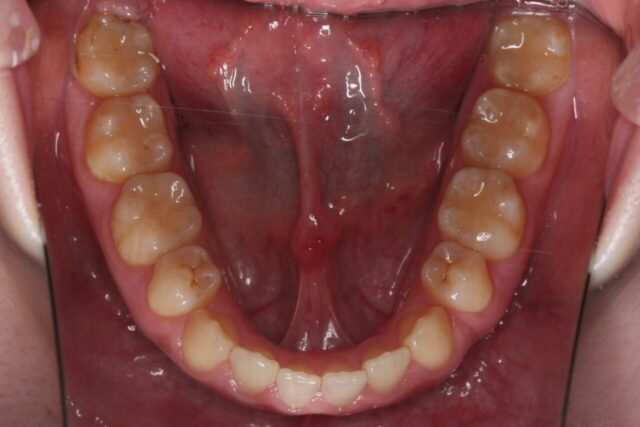

【15歳男性】すきっ歯と出っ歯を治したい(非抜歯治療)

〖主訴〗:すきっ歯と出っ歯が気になる。

主症状:空隙歯列、正中離開、上顎前突

初診時年齢:15歳 男性

動的治療期間:1年9ヵ月

治療内容:非抜歯治療にて出っ歯を改善した症例です。出っ歯を改善するため、上顎には矯正用アンカースクリューを使用し奥歯を固定することで、歯の隙間を閉じながら出っ歯の改善を行い、下顎は歯列を拡大し歯牙の配列を行い、上下の幅径の調和をはかり適切な咬合関係が得られました。

治療に用いた主な装置:マルチブラケット装置など治療費(税込):矯正費77万円 毎回の処置料5,500円

治療におけるリスク:治療中の歯の痛みや歯肉退縮、歯ブラシが不十分であると治療中に虫歯や歯肉炎をおこし、治療期間も余計にかかる心配があります。また、装置撤去後に保定装置をきちんと使用しないと後戻りを起こします。正中離開は後戻りをしやすいため、保定装置の使用が大切です。 -